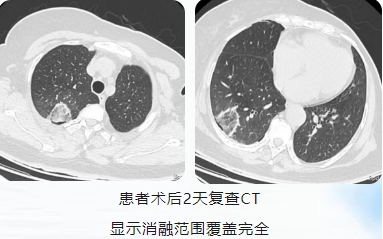

手术过程中,医生团队在局麻下经CT扫描后精确定位,将射频消融针准确穿刺至病灶核心区域。消融过程中采用50w功率分别对右肺上叶及右肺下叶病灶消融5min,CT实时扫描显示,病灶周围形成特征性的“治疗性晕征”,表明病灶已被完全覆盖消融。全程患者保持清醒状态,无明显不适感。

影像资料

左肺上叶病灶消融术后

36个月复查病灶缩小呈瘢痕改变